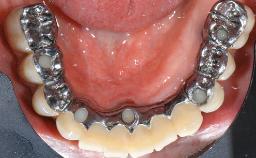

In 2004, the patient, a smoker, began dental treatment at the ACTA graduate clinic. She was a TV producer exposed to a lot of stress in her job and had a sick husband. Her maxillary teeth had been extracted, as had the mandibular canines, premolars, and molars, with the exception of tooth 34. She received a complete maxillary denture and a mandibular skeleton denture. In October 2007, her maxilla was augmented by an oral and maxillofacial surgeon; in March 2008, implants (Biomet 3i, Palm Beach, Florida, USA) were inserted at that same clinic. In 2008, the patient was presented at the Department of Oral Implantology and Prosthetic Dentistry to request restorations for her implants. An implant-supported overdenture was planned. She also asked if we could restore her occlusion with fixed prosthetics.